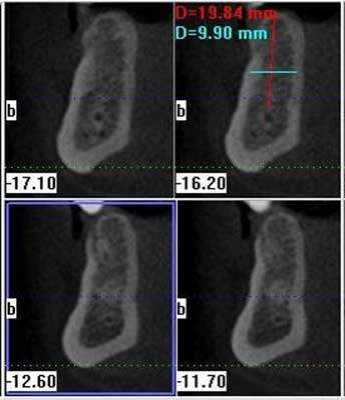

The power of cross-sections and precise measurementsCommunicating with conviction is also a key to treatment acceptance. The detail provided by cone beam images takes the guesswork out of implant planning. Dentists without 3-D images must account for the scenarios that sometimes pop up as a result of conditions that we cannot discern from less detailed imaging options. They must inform the patient that the treatment plan may change, depending on what is discovered during the first surgical session. Discussing these “what-if’s” with the patient leads to doubt and procrastination. A cone beam scan offers a view of the details that were previously only visible during surgery. When patients comprehend their condition, they are more eager to begin treatment quickly. Cone beam helps there too. Since my GXCB-500™ unit fits right in our office, the patient can go from imaging to diagnosis to treatment in less time. With in-house 3-D capability, my communication for implant planning and placement has also improved with referring dentists who want to stay current with their patient’s progress. To facilitate this, I print out a screenshot of the patient’s dentition and e-mail it to the referring dentist, or send a CD with the imaging software and the scans. If the referring dentist wants to discuss the situation, all the facts are on both of our computers in 3-D, but often the clarity of the images removes any doubts. These dentists are happier because they don’t want their patients to have any surprises during treatment that may affect them later either.